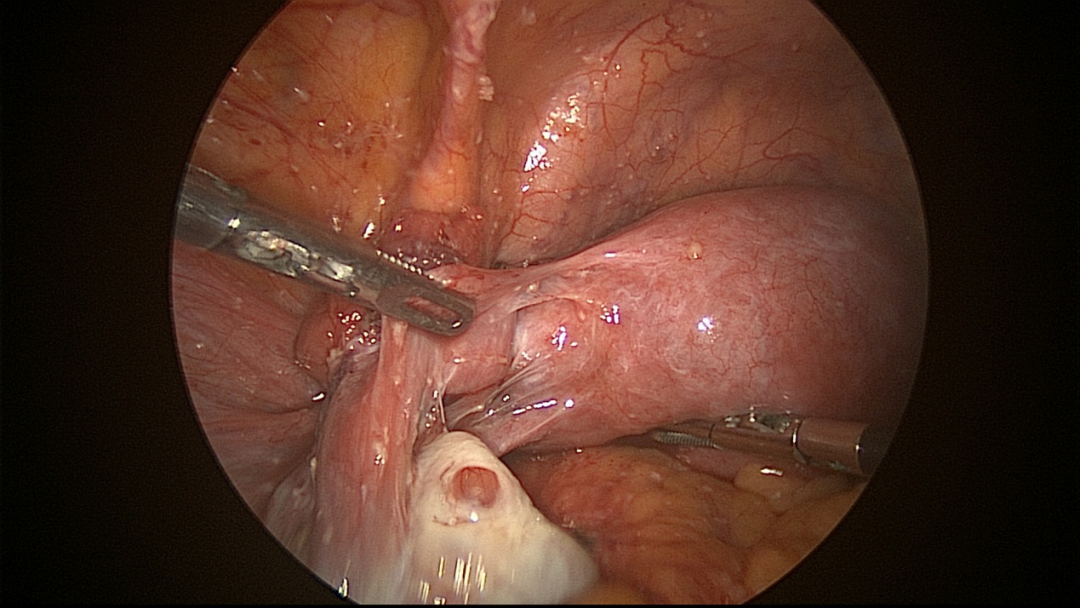

赵秋生主任建议像欢姐这种情况,如果多次试管失败,或者不明原因性不孕,如果还没有经过任何一次手术排查原因的话,那真的可能不是不明原因性的,而是不孕原因还没有逐一排查到位,因为女性的内生殖器官位于盆腔内,很多患者表现了轻微症状或者根本没有明显不适症状,但却做足备孕措施仍然不孕,达1年以上就要认真排查原因了,当所有的理化检查未能找出病因时,第一时间要考虑行宫腹腔镜联合探查术。经专家组讨论后,欢姐就在入院第二天进行了宫腹腔镜联合探查手术,术中得以揪出元凶。

△赵主任带领团队进行宫腹腔镜手术

腹腔镜检查有重大发现,腹腔镜检查显示腹膜和网膜上有密集的白色粟粒状结节(如图1所示):

△图1腹膜和网膜上白色的粟粒状结节

大网膜与左前壁腹膜广泛膜状粘连;右侧输卵管与卵巢膜状粘连。左侧输卵管扭曲,与侧腹膜、同侧卵巢粘连(如图2所示)。

△图2腹壁及左侧附件情况